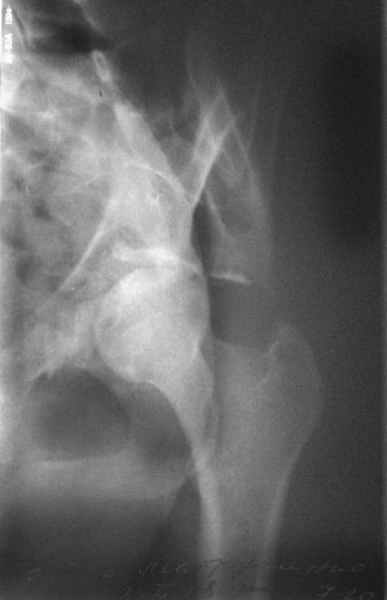

прикладываю схему доступа и случай.